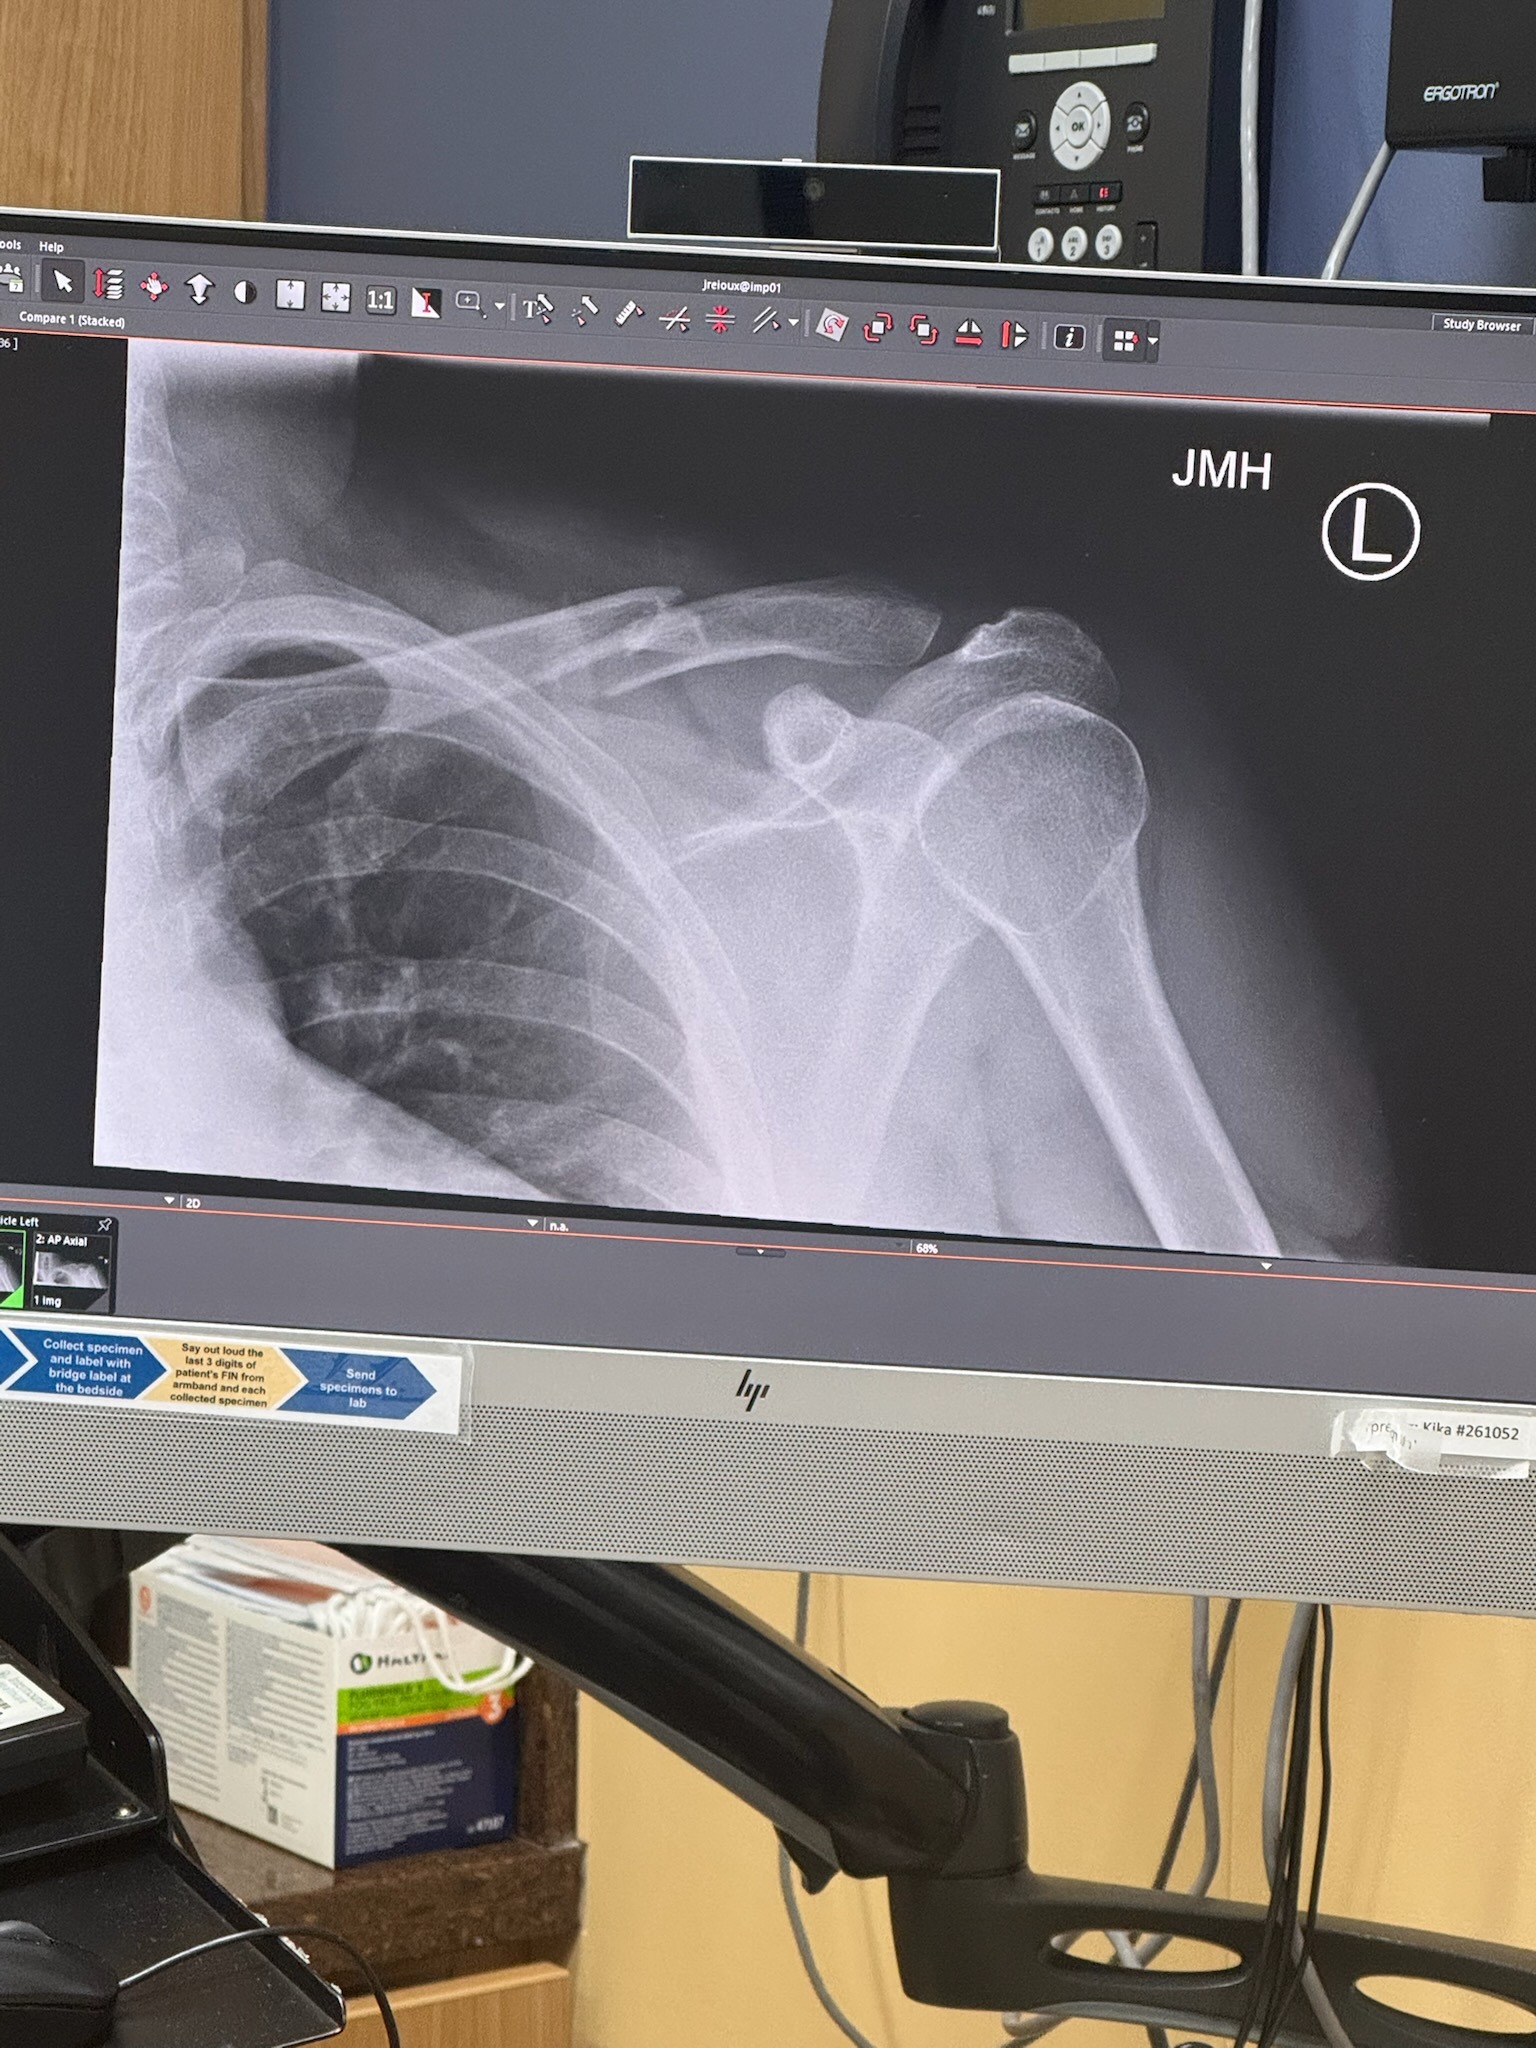

On August 10, 2025, Augusto was in a motorcycle accident. His tire locked up and he veered off road into the ravine. Augusto was taken by ambulance to the Park City hospital. He suffered two fractures to his clavicle. A puncture wound on his left elbow that needed 5 stitches, abrasions on his left leg, left arm and back.

Augusto is home and in a lot of pain and will need to have surgery to repair his clavicle, placing a metal plate and screws to allow the bone to stabilize.

Em 10 de agosto de 2025, Augusto sofreu um acidente de moto. Seu pneu travou e ele saiu da estrada e caiu em um barranco. Augusto foi levado de ambulância para o hospital de Park City. Ele sofreu duas fraturas na clavícula. Uma perfuração no cotovelo esquerdo que precisou de 5 pontos, além de escoriações na perna esquerda, braço esquerdo e costas.

Augusto está em casa, com muita dor e precisará passar por uma cirurgia para reparar a clavícula, com colocação de uma placa de metal e parafusos para estabilizar o osso.

El 10 de Agosto de 2025, Augusto tuvo un accidente en su motocicleta. Su rueda trasera se bloqueó haciendo que él perdiera el control y terminara cayendo fuera de la carretera en un barranco. Augusto fue llevado por una ambulancia hasta el hospital de Park City-Utah. Él sufrió dos fracturas en su clavícula. Una herida punzante en su codo izquierdo que necesitó de 5 puntos para cerrar y daños en su pierna izquierda, brazo izquierdo y espalda.

Augusto está en casa con mucho dolor y necesitará cirugía para reparar su clavícula con una aleación de metal que le permitirá estabilizar el hueso.